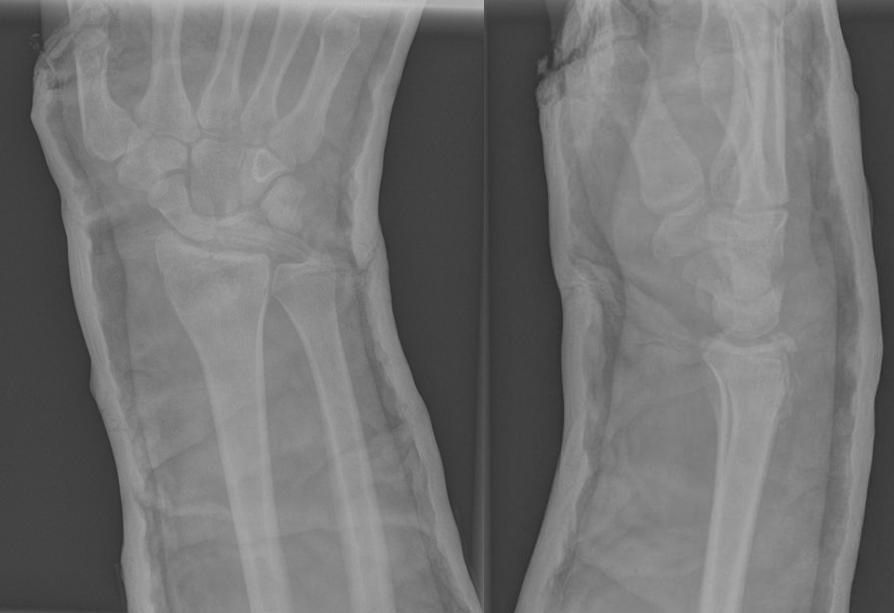

Коллеги, спасибо большое за Ваше активное участие и советы. Прилагаю снимок через 7 суток.

Прикольно! Обсуждали луч, а на контроле - голень! Метаморфоза однако!